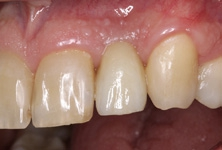

Der klinische Befund zeigte eine definitive Versorgung auf 12 und eine temporäre Versorgung auf 22. Dahingegen lag bei der Implantatversorgung in regio 22 der Verdacht auf eine partielle Fibro-Osseointegration vor (Abb. 1 und 2) [9,10].

Nach einer Ästhetikeinprobe wurde die Zirkoniumdioxidkrone mit Multilink Hybrid Abutment Zement (Ivoclar Vivadent) auf dem PEKK-Abutment verklebt (Abb. 25–28). Die Klebeüberschüsse wurden entfernt, die subgingivalen Anteile sorgfältig poliert und gereinigt. Die Abbildung 29 zeigt das individuell ausgeformte Weichgewebsprofil vor der definitiven Insertion der Hybridabutmentkrone, die mithilfe einer neuen Titanabutmentschraube eingesetzt wurde. Nach dem Einsetzen der Versorgung mit 25 Ncm wurde eine Röntgenkontrollaufnahme angefertigt. Da das Hochleistungspolymer nicht röntgenopak ist, bedarf es etwas Erfahrung bei der Passungskontrolle. Die Aufnahme sollte im rechten Winkel zur Plattform auftreffen, um dann eine parallel verlaufende dunkle Scheibe in einer Höhe von 0,55 mm über dem Implantat zu erkennen (Abb. 30 und 31). Mithilfe von Zusätzen, wie z. B. Bariumsulfat, könnte der Hochleistungskunststoff röntgenopak gefertigt werden. Allerdings würden diese das Material schwächen, wodurch die herausragenden Eigenschaften von PEKK, wie Stabilität, Duktilität und Abdichtung, minimiert würden. Beim Followup nach zwölf Monaten zeigten sich eine stabile Weichgewebesituation und geschlossene Interdentalräume (Abb. 32).